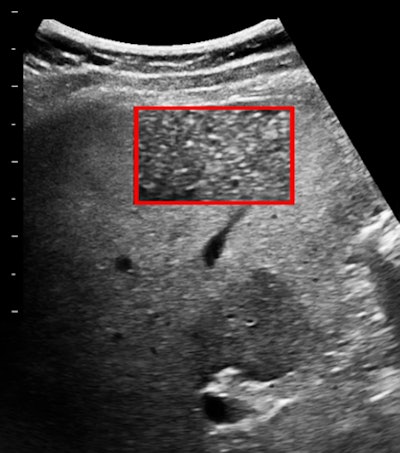

Lots of tiny patches of collagen make liver parenchyma appear coarse or heterogeneous and attenuation is increased markedly. What I like to do is to make magnification views of small regions of hepatic parenchyma, usually 5 to 7 MHz per custom and at 15 to 18 MHz when that is practical. Fibrosis is indicated by bright spots in the field-of-view.

I export liver images into my computer and open them one at a time in ImageJ. I select a region of interest. Often I will alter the brightness and contrast or bit depth before I look at the texture pattern.

This is a simple kind of contrast-enhancing and noise-reducing form of grayscale remapping. The real beauty of this preconditioning of images is in additional semiquantitative routines.

Below are images of another patient.

What have you decided about this case? My report was of fatty liver (with a spared normal region) with the beginning of fibrosis. This was confirmed histologically.

I started a little feasibility project that included 50 patients for whom I was able to get some additional clinical and lab information. There was excellent separation of normal livers, fatty livers, and those with fibrosis on visual criteria alone. The standard deviation in the grayscale histogram was the best single numerical discriminator and grader. Ultrasound elastography was not contributory. To be fair, I was seeing healthy ambulatory outpatients, which is pretty far removed from inpatients with established and advanced liver disease.